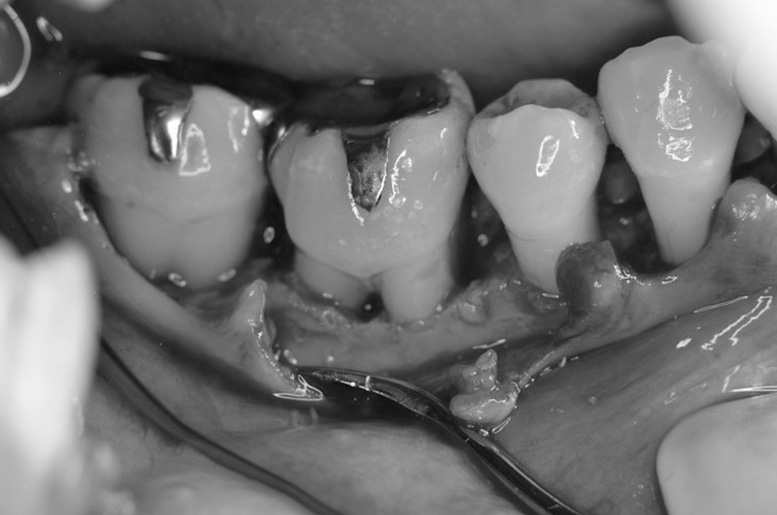

歯周再生療法 精密根管治療 歯周矯正治療 ジルコニアセラミック治療